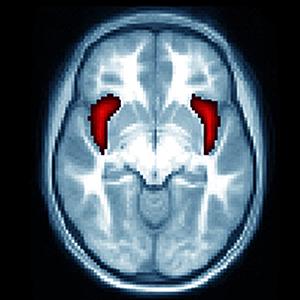

In school-age children previously diagnosed with depression as preschoolers, a key brain region involved in emotion is smaller than in their peers who were not depressed, scientists have shown.

The research, by a team at Washington University School of Medicine in St. Louis, also suggests that the size of the brain's right anterior insula may predict the risk of future bouts of depression, potentially giving researchers an anatomical marker to identify those at high risk for recurrence.

There is one insula on each side of the brain, and they are thought to be involved in emotion, perception, self-awareness and cognitive function.

The insula also is smaller in depressed adults compared with those of their peers who are not depressed. By using MRI scans and focusing on brain anatomy, the researchers hope to find clues to better diagnose and treat depression and to identify individuals at higher risk for recurrent episodes.

As part of the study, the investigators also found the same brain structure is smaller in kids diagnosed with pathological guilt during their preschool years, providing evidence that excessive guilt is a symptom of depression related to the size of the insula.

The researchers found that children with a smaller insula in the right hemisphere of the brain -- related either to depression or excessive guilt -- were more likely to have recurrent episodes of clinical depression as they got older.